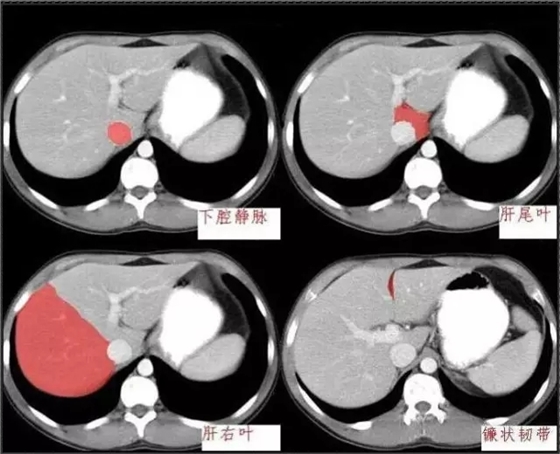

640.webp.jpg